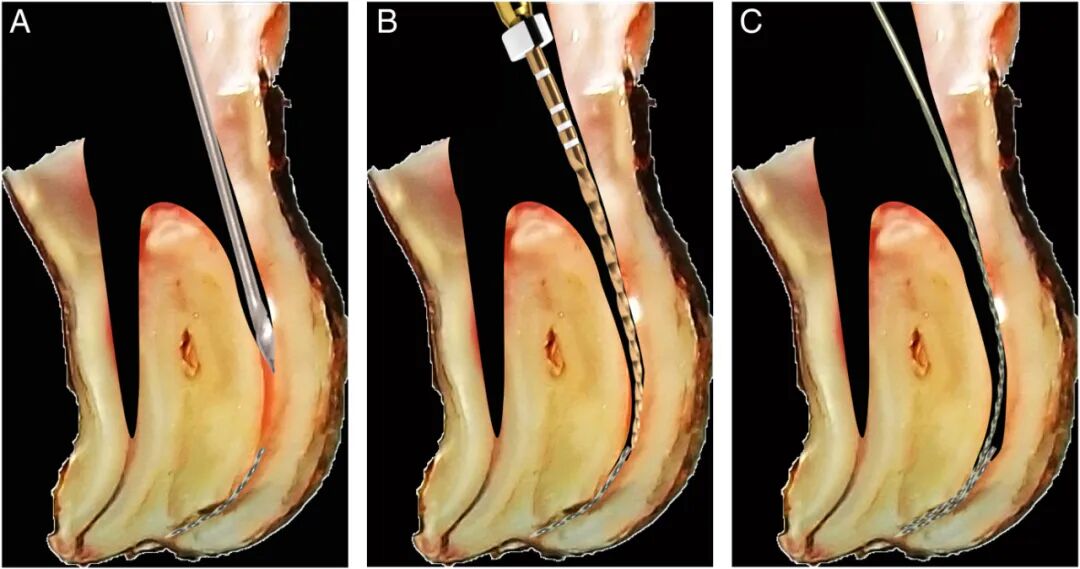

图3. (A)初始位置的脊髓针。(B)推动针芯的脊髓针。(C)脊椎针卡住折断器械。